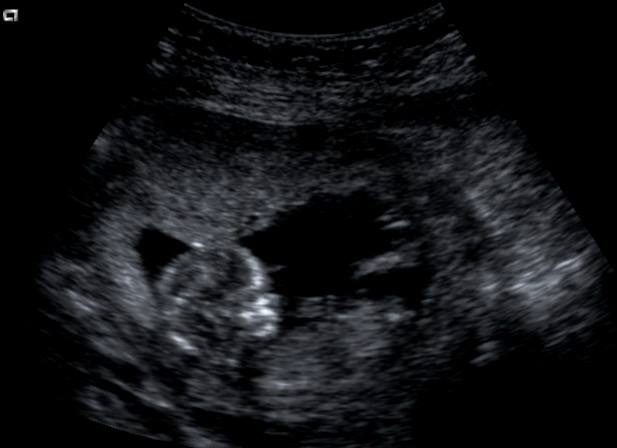

Im going to guess girl from the 3rd picture.

Guessing girl from the 3rd pic too!

I'm not seeing a nub at all.

Lovemy4, you don't? Isn't the nub the white thingy pointing downwords?